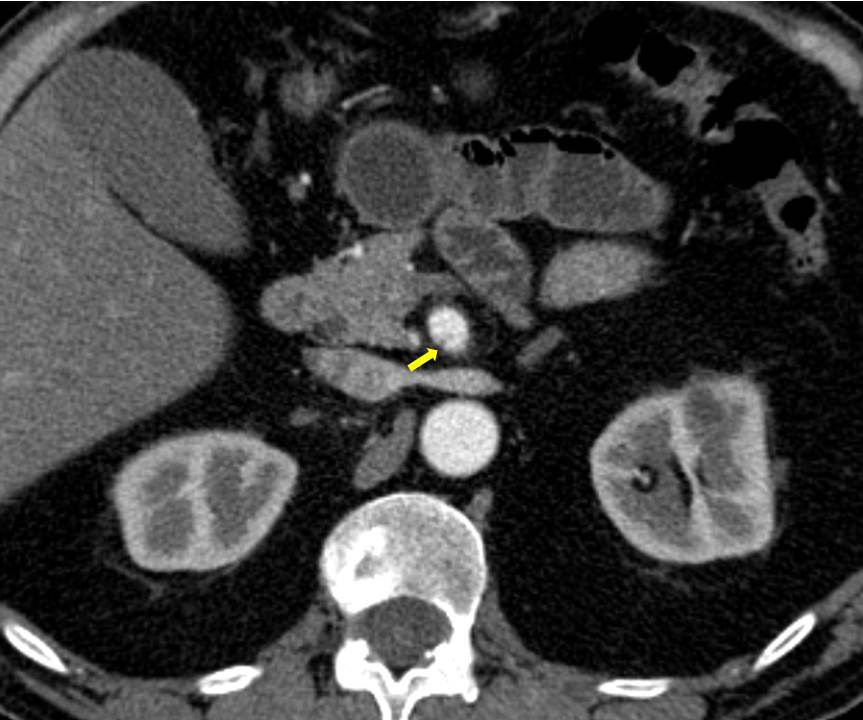

Acute abdominal pain is one of the most common conditions encountered in the emergency department. The differential diagnosis of acute abdominal pain is extensive and identifying the underlying etiology can be challenging. We report a case of acute transient ischemic jejunitis due to symptomatic isolated superior mesenteric artery dissection in a patient with no cardiovascular risk factors or autoimmune diseases. Symptomatic isolated superior mesenteric artery dissection is a rare cause of acute abdominal pain usually treated in the surgical department. The patient had criteria for conservative treatment and rapidly recovered. We highlight a rare condition which should be taken into account for the differential diagnosis of acute abdominal pain.